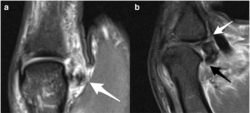

The white arrow in image (a) points to Stener lesion – the dislocated distal stump that is retracted proximally and wrapped around the adductor pollicis aponeurosis (yo-yo on a string appearance). Sagittal image demonstrates concomitant complete disruption of the volar ligaments, the checkrein (black arrow), and phalangoglenoid ligaments (white arrow).